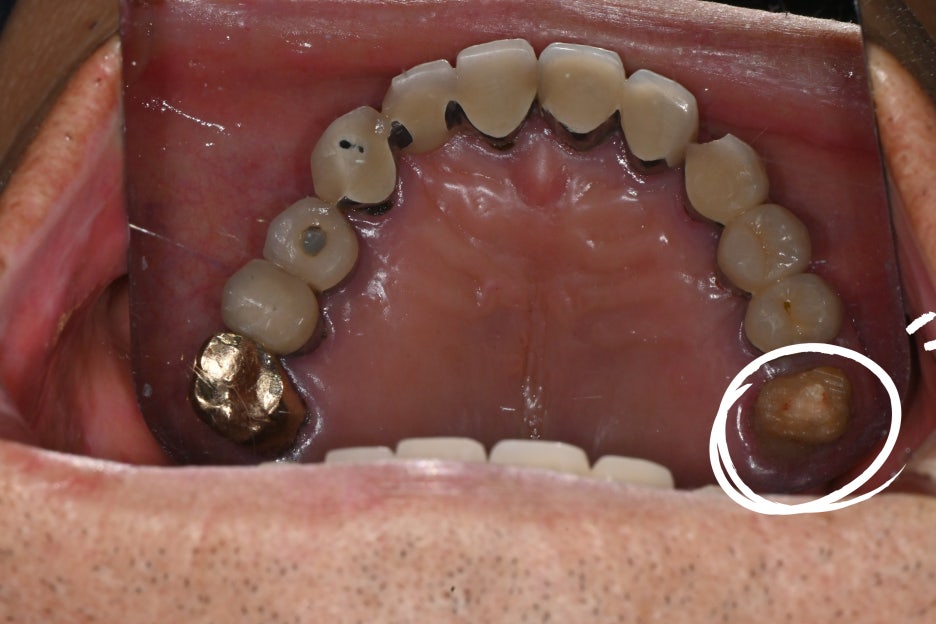

환자분의 어금니는 보철물 아래로

충치가 진행되어 치아 뿌리 근처까지

손상된 상태였기 때문에

신경치료가 필수적이었습니다.